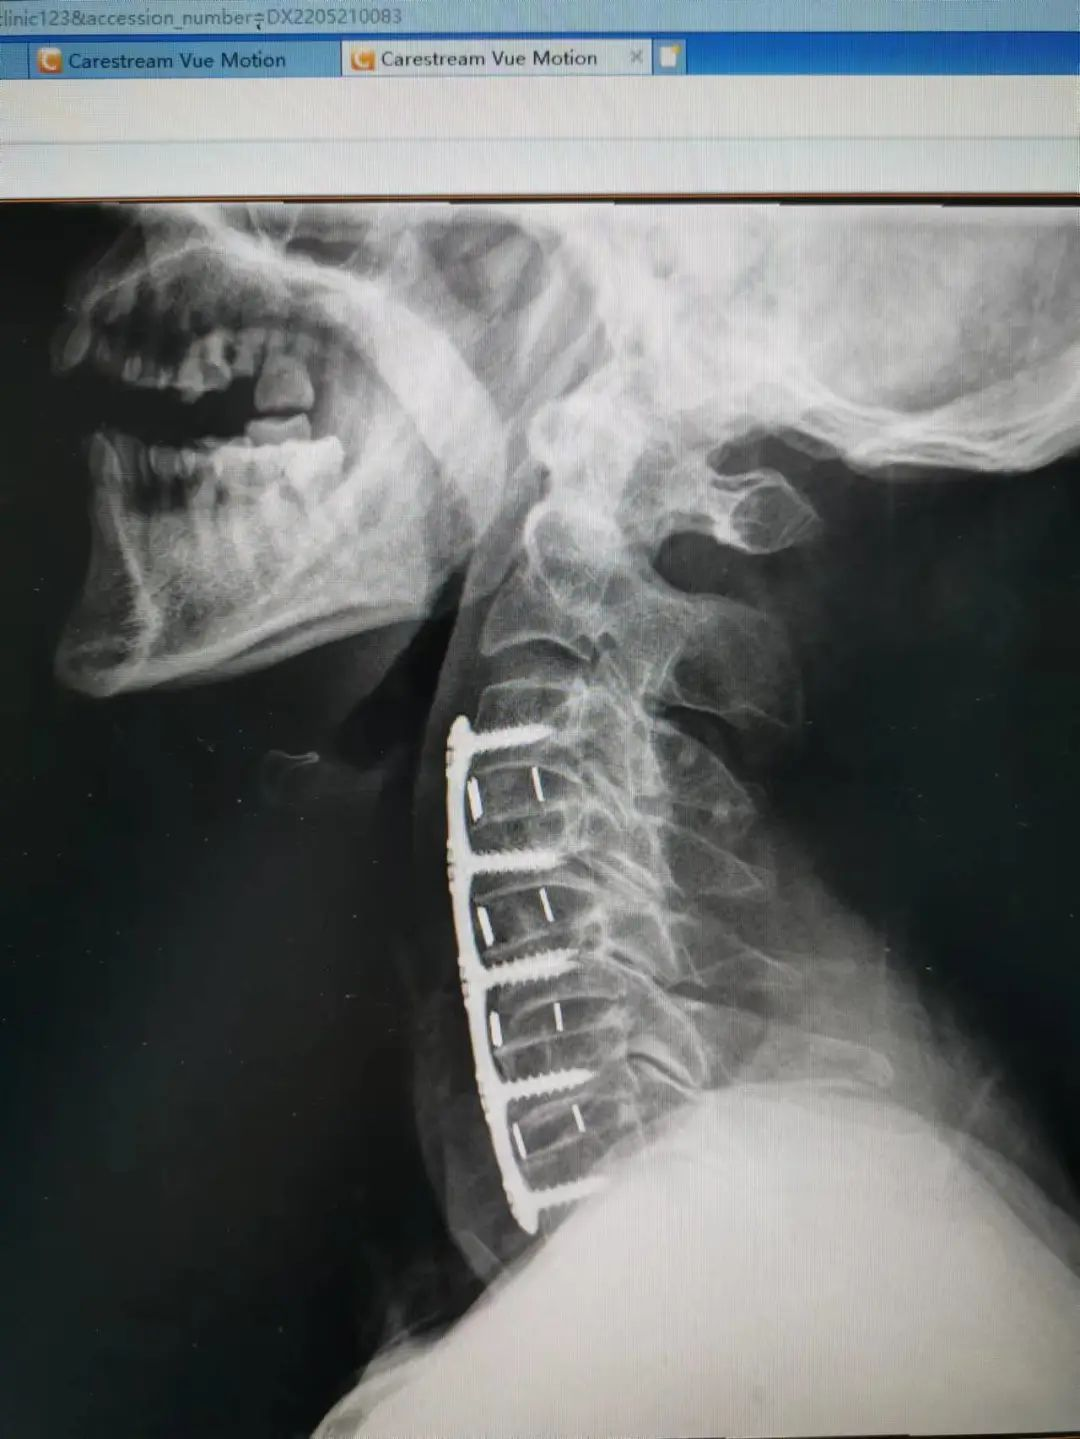

由于楊先生的病情嚴重,需住院治療。楊先生入院后,瀘州市中醫(yī)醫(yī)院骨傷二科科主任楊陳一制定了手術計劃,決定脊髓型頸椎病的手術從前路切開減壓,頸3/4 、頸4/5、 頸5/6、 頸6/7椎間盤切除,椎間融合,鋼板內固定術手術,而腰椎管狹窄癥經后路切開減壓,腰3/4、腰4/5椎同盤動除,椎間融合、釘棒系統(tǒng)內固定術。

楊先生術后拍片